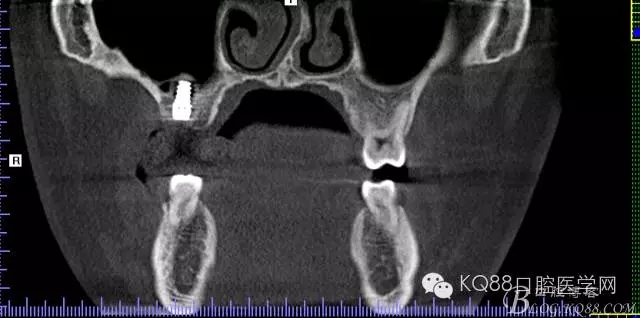

植入后,CBCT

另外一個(gè)切面。竇底粘膜完整連續(xù)??梢钥吹缴舷乱Ш系奈恢藐P(guān)系。

下面兩張是種植前后的對(duì)比片子。

手術(shù)前

手術(shù)后。